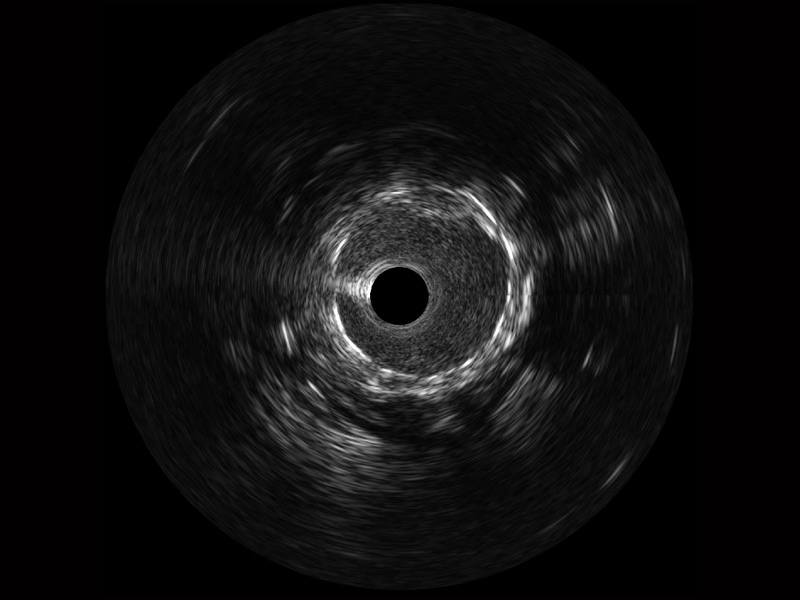

传统IVUS图像

对比传统IVUS导管成像,milan米兰宽频IVUS图像的近场支架梁显影更细腻,远场中膜外血管仍清晰可辨,兼顾远中近,兼顾分辨力与穿透深度